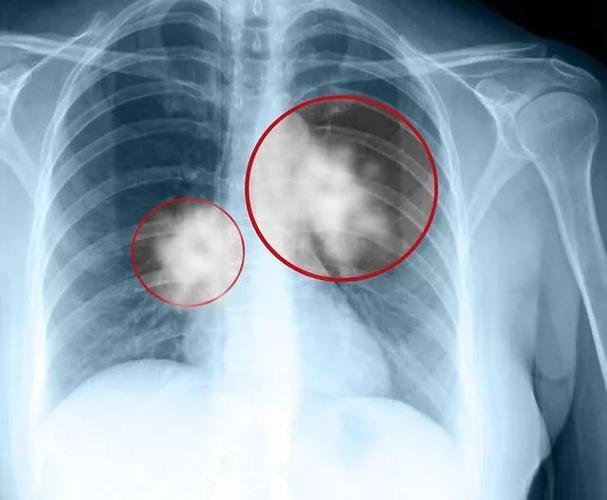

1. 低剂量螺旋CT:金标准筛查

· 辐射量仅是常规CT的1/5

· 可发现直径2mm的微小结节

· 40岁以上高危人群建议每年1次

45岁的银行职员王女士在体检中发现5mm磨玻璃结节,经胸腔镜微创手术确诊为原位癌,术后3天出院,无需放化疗。